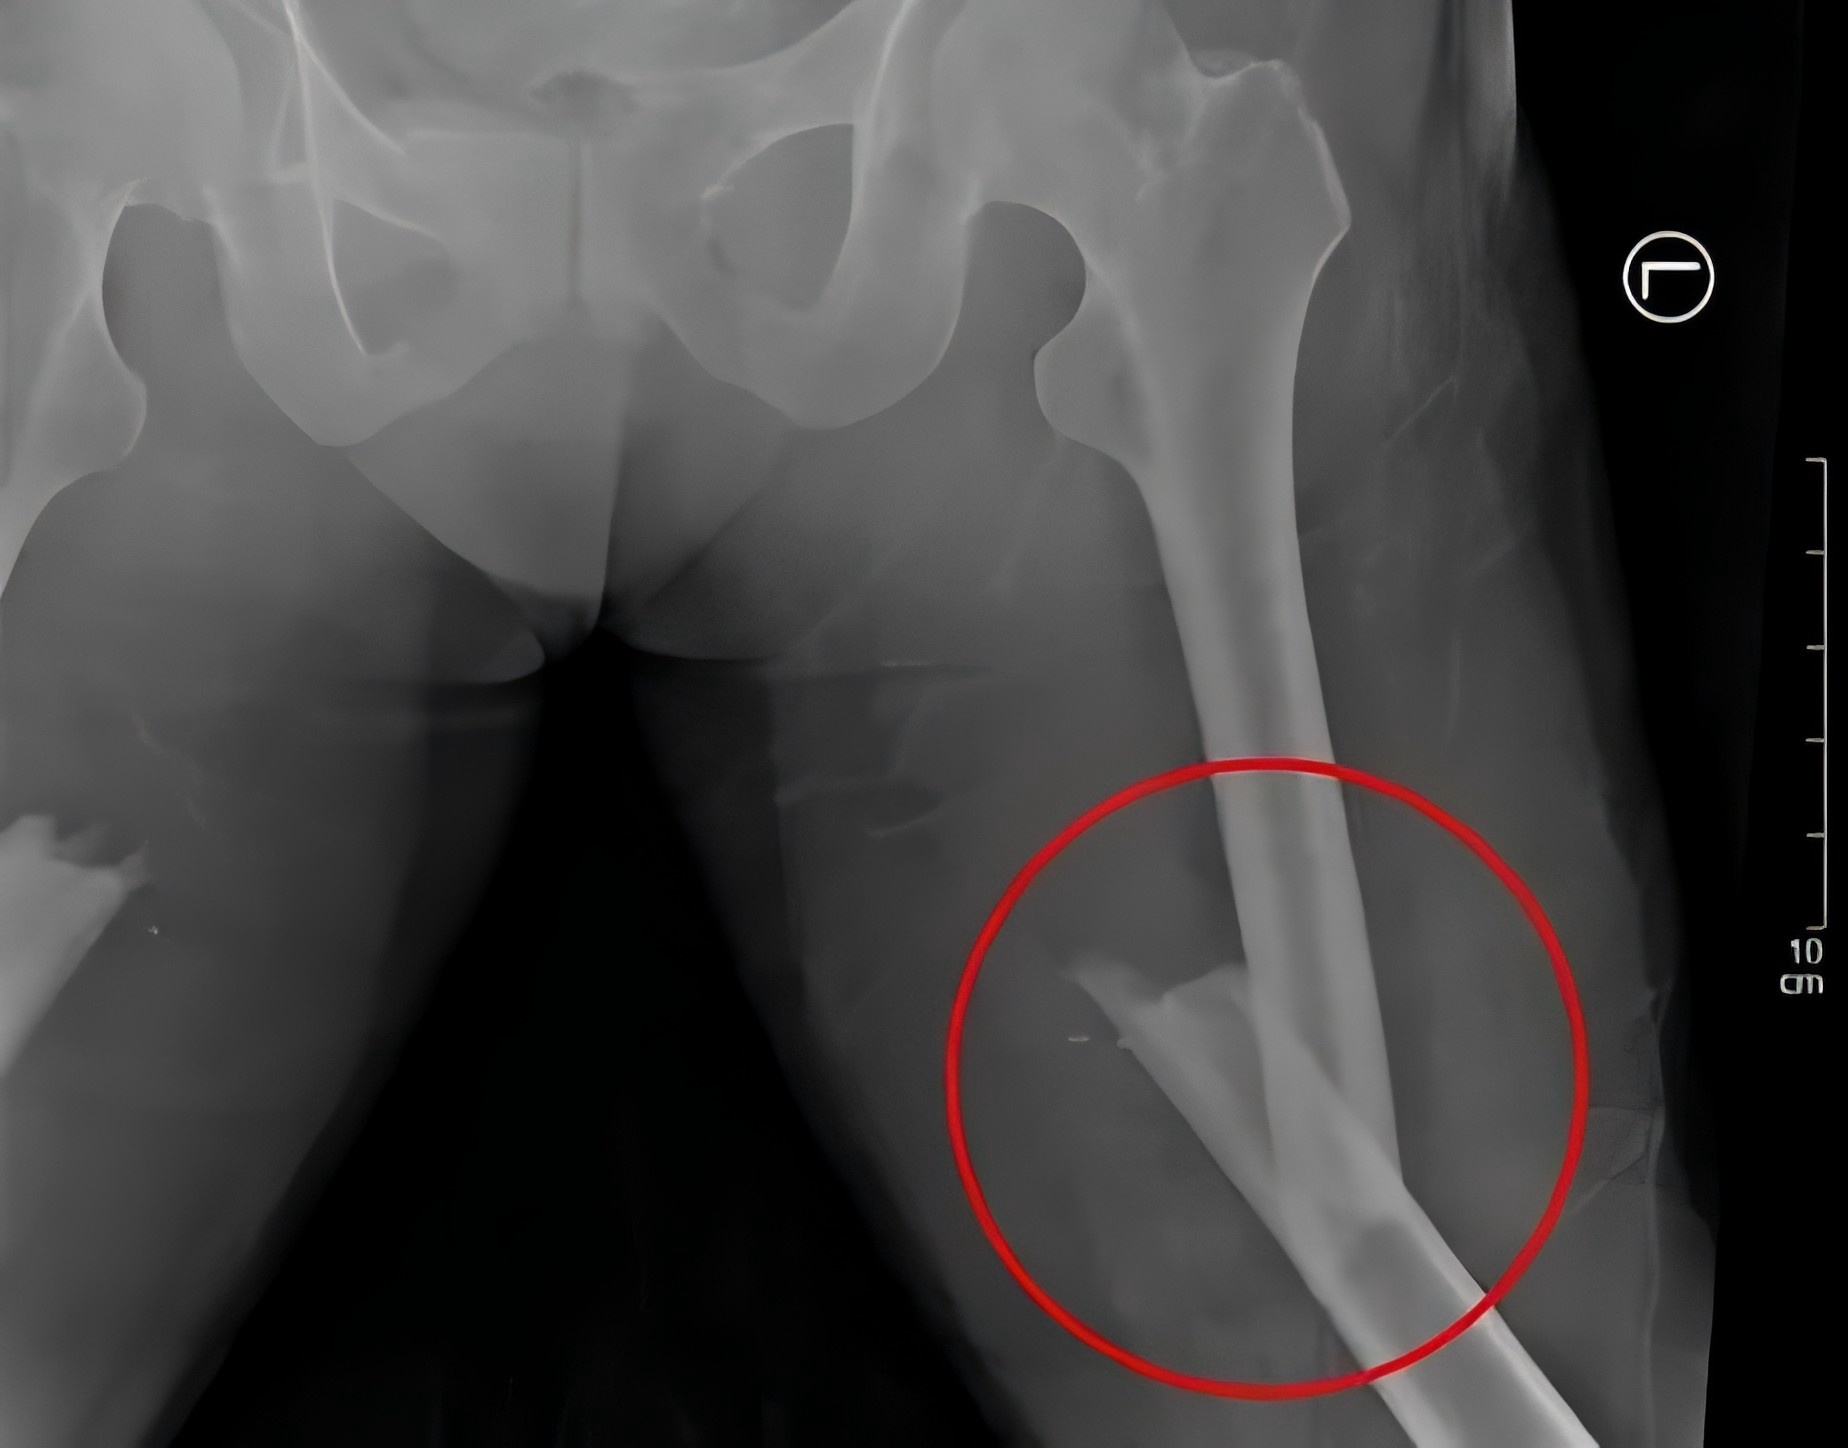

全力以赴救治重傷患者

2月28日,48歲的戴某不慎被重物(重量約為2噸)砸傷,導致多發(fā)性骨盆骨折、右側(cè)粉碎性髂骨骨折、雙側(cè)股骨骨折、右側(cè)腓骨骨折等多處損傷,尤其是骨盆處幾乎“散架”,患者失血性休克,生命垂危。

殷小軍團隊基于損傷控制理念,為患者量身定制了微創(chuàng)手術(shù)方案。手術(shù)分為兩期進行:待患者生命體征穩(wěn)定后,一期先行骨盆及一側(cè)股骨骨折微創(chuàng)內(nèi)固定治療;二期行另一側(cè)股骨骨折微創(chuàng)內(nèi)固定手術(shù)。

(患者術(shù)后X片)